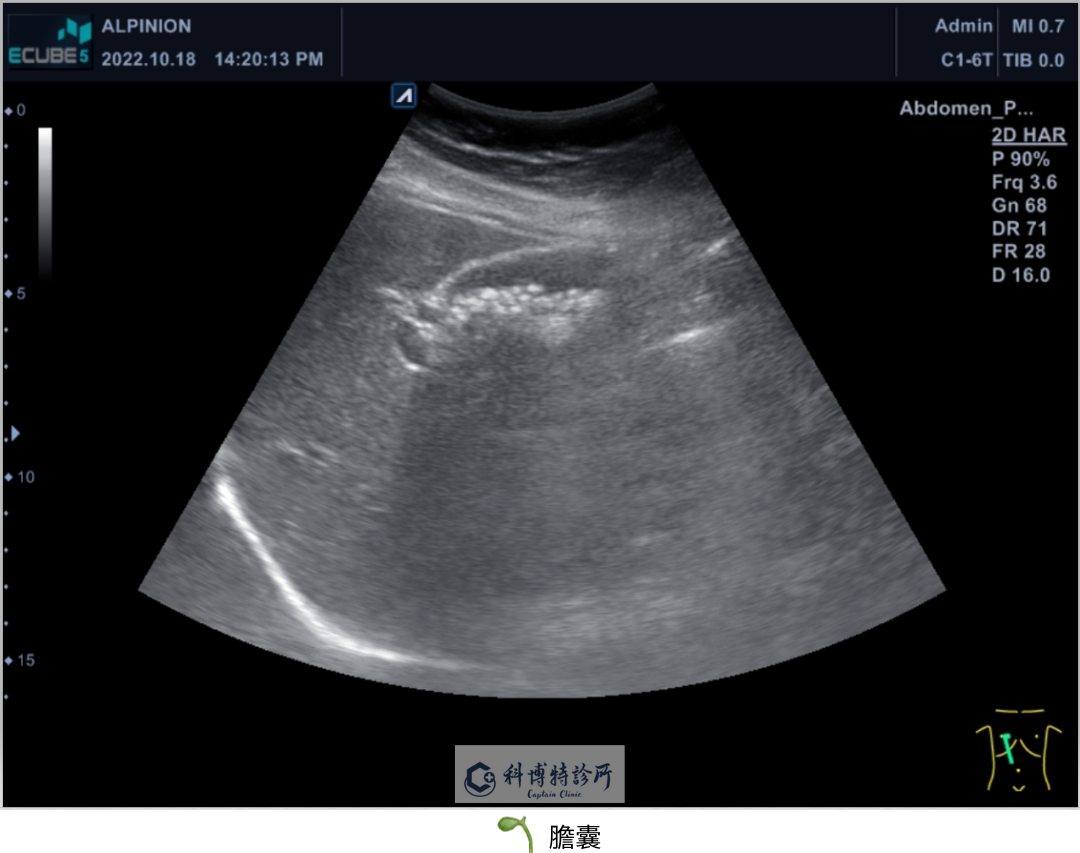

腹部超音波主要是檢查上腹部的肝臟、膽囊、部分胰臟、脾臟、腎臟以及附近血管等。利用超音波回音將影像投射螢幕,檢查腹部臟器是否有異常之處。需特別注意的是做腹部超音波檢查時需空腹,主要是因為空腹時膽囊會脹大,較可看清楚膽囊情況。

。膽:膽囊結石、膽囊息肉、急慢性膽囊炎、膽道阻塞、腫瘤等